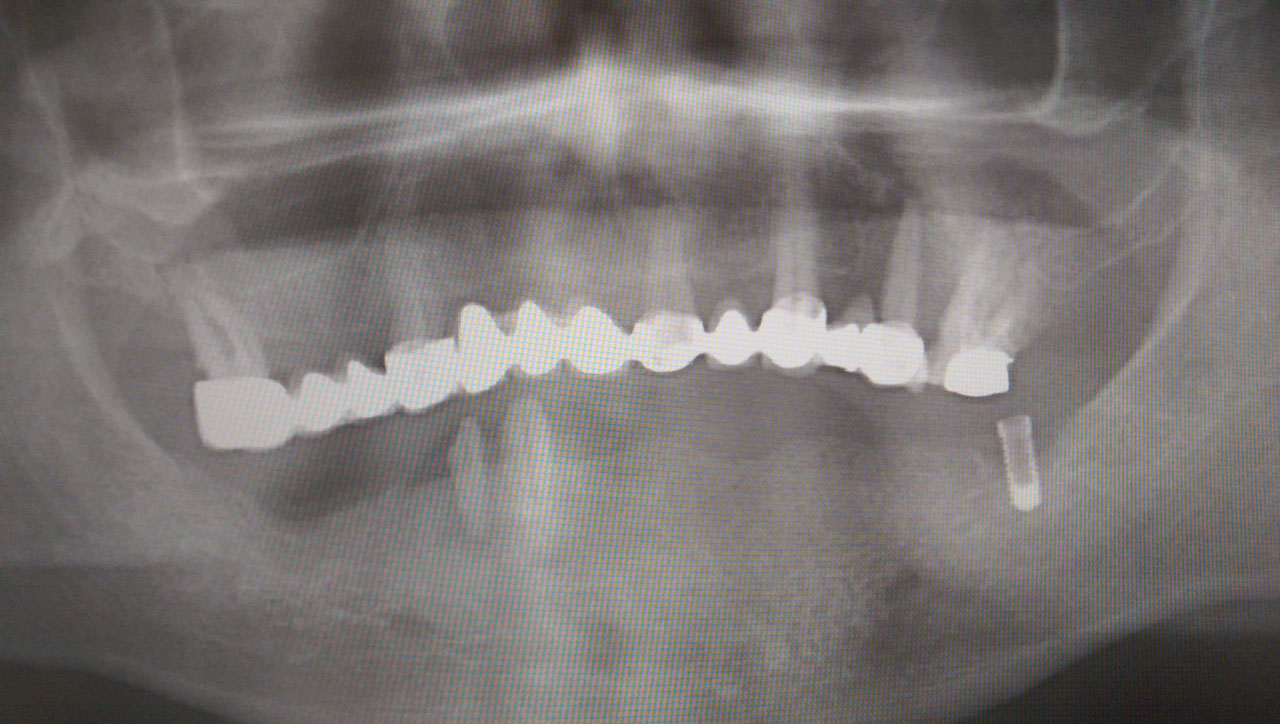

Alsó állcsont teljes rehabilitációja 72 óra alatt

Alsó állcsont teljes rehabilitációja 72 óra alatt, azonnal terhelhető implantátumokkal súlyos paradontitisben szenvedő dohányzó páciens esetében. Az alsó állcsont fogai mind mozogtak az előrehaladott fogágypusztulás miatt.

A fogakat eltávolítottuk, a gyulladt, fertőzött csontot kitakarítottuk, kifertőtlenítettük, majd azonnal implantáltunk.

Svájci, IHDE márkájú, azonnal terhelhető implantátumokat helyzetünk be, és ezekre harmadnapra rögzített, hosszútávú, fémvázas, esztétikus műanyaggal leplezett hidat ragasztottunk be.

Ezt az ideiglenes hidat a sebek gyógyulása miatt használjuk, de tartóssága miatt véglegesként is használható. A legtöbb esetben, ahogy itt is, 6 hónap múlva porcelán hídra cseréljük, a teljes gyógyulás után.